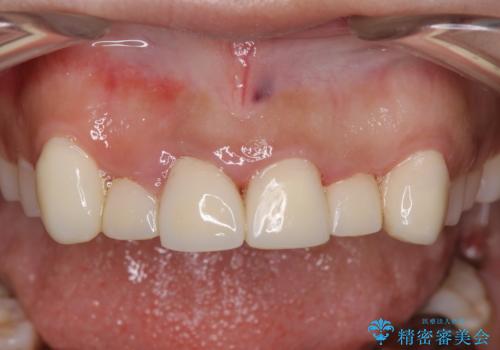

歯周組織がある程度改善されるまでに3か月ほどかかりました。

いざ型どりしていくというタイミングで、前歯の大きさが違いすぎるのが気になるとのことで歯周外科治療(アピカリ)にて歯肉のラインを整えることに。

歯肉の治りを待ったうえで(約8か月)、最終補綴することとなりました。